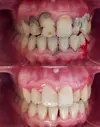

Ortodonti, dişsel çapraşıklıklar, çene yüz iskeletsel bozukluklar, estetik dolgu, protez, metal ve zirkonyum kaplama, E-MAX, implant tedavisi, dolgu, kanal tedavisi, diş çekimi yapılmaktadır. 7/24 nöbetçi diş hekimi olarak da kliniğimiz açıktır.

Diş Çürükleri

Diş Çapraşıklığı